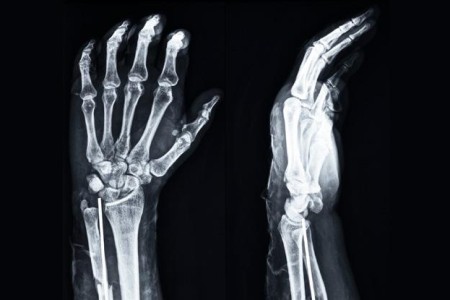

Wrist X-Ray

Read More

X-Ray